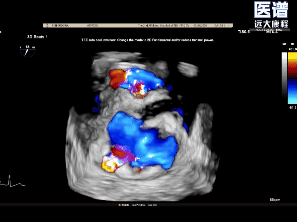

TEE-2D血流

TEE-3D血流

重度DMR,LVEF 61%,LVIDd 5.62cm,LVIDs 3.27cm,VCW 0.72cm,EROA=0.47cm2;RV=83ml,PG mean 3mmHg,PASP 51mmHg。

病变位置为:A1邻近交界处脱垂;宽度/高度:1.08cm/0.29cm;A1/P1瓣叶长度:1.38cm/1.17cm;前后径(AP直径):3.56cm;二尖瓣口面积:4.39cm2